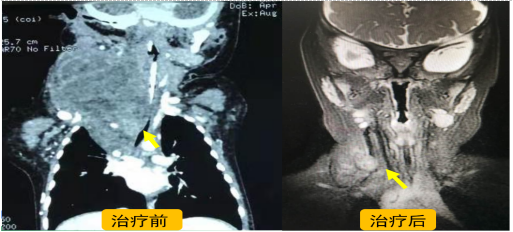

病例2:6个月男孩,颈部巨大肿物压迫气道导致呼吸困难,外院诊断为颈部淋巴管畸形,因范围太大辗转求治无果,经我院MDT门诊会诊讨论后制定治疗方案:超声引导下淋巴管畸形微波消融+药物注射+口服西罗莫司8个月,呼吸及外观完全恢复正常,避免了气管切开及手术切除创伤。

图3 颈胸部淋巴管畸形